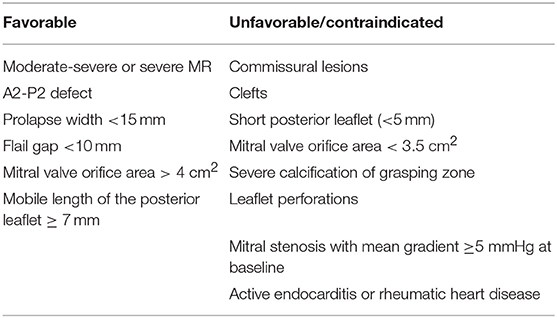

Both TTE and TEE should be reviewed by the Heart Team to confirm eligibility and intraprocedural approach to MV repair. Agreement should be made as to the precise location for device placement, number of device, and treatment strategies, particularly with more challenging anatomy as defined in Table 1.

Transesophageal echocardiography (TEE) is the mainstay for MR intervention screening because of its key role in intraprocedural guidance. A careful examination of the mechanism of MR and quantitative assessment of MR degree of severity should be reported. In addition to the standard 2D echocardiographic views, utilization of advanced imaging is particularly helpful to determine the presence of anatomic abnormality. The use of multiplane imaging allows a systematic visualization of all MV scallops, from the medial to lateral aspects of the MV (Figure 1). An en-face view of the atrial side of the entire MV (surgeon's view) and adjacent structures is possible using 3D imaging. Flail and prolapse segments, the location of clefts, deep indentations, perforations and significant malcoaptation gaps may be more apparent and easier to visualize. In addition, MV area can more precisely be measured (Figure 2).

Figure 1. Multiplane view of the mitral valve. Mid-esophageal biplane views (left panel: 60 degree view, right panel: 150 degree view) of the mitral valve leaflets. The blue arrow demonstrates the medial aspect of the mitral valve, the orange arrow, the central aspect and the red arrow, the lateral aspect of the mitral valve.